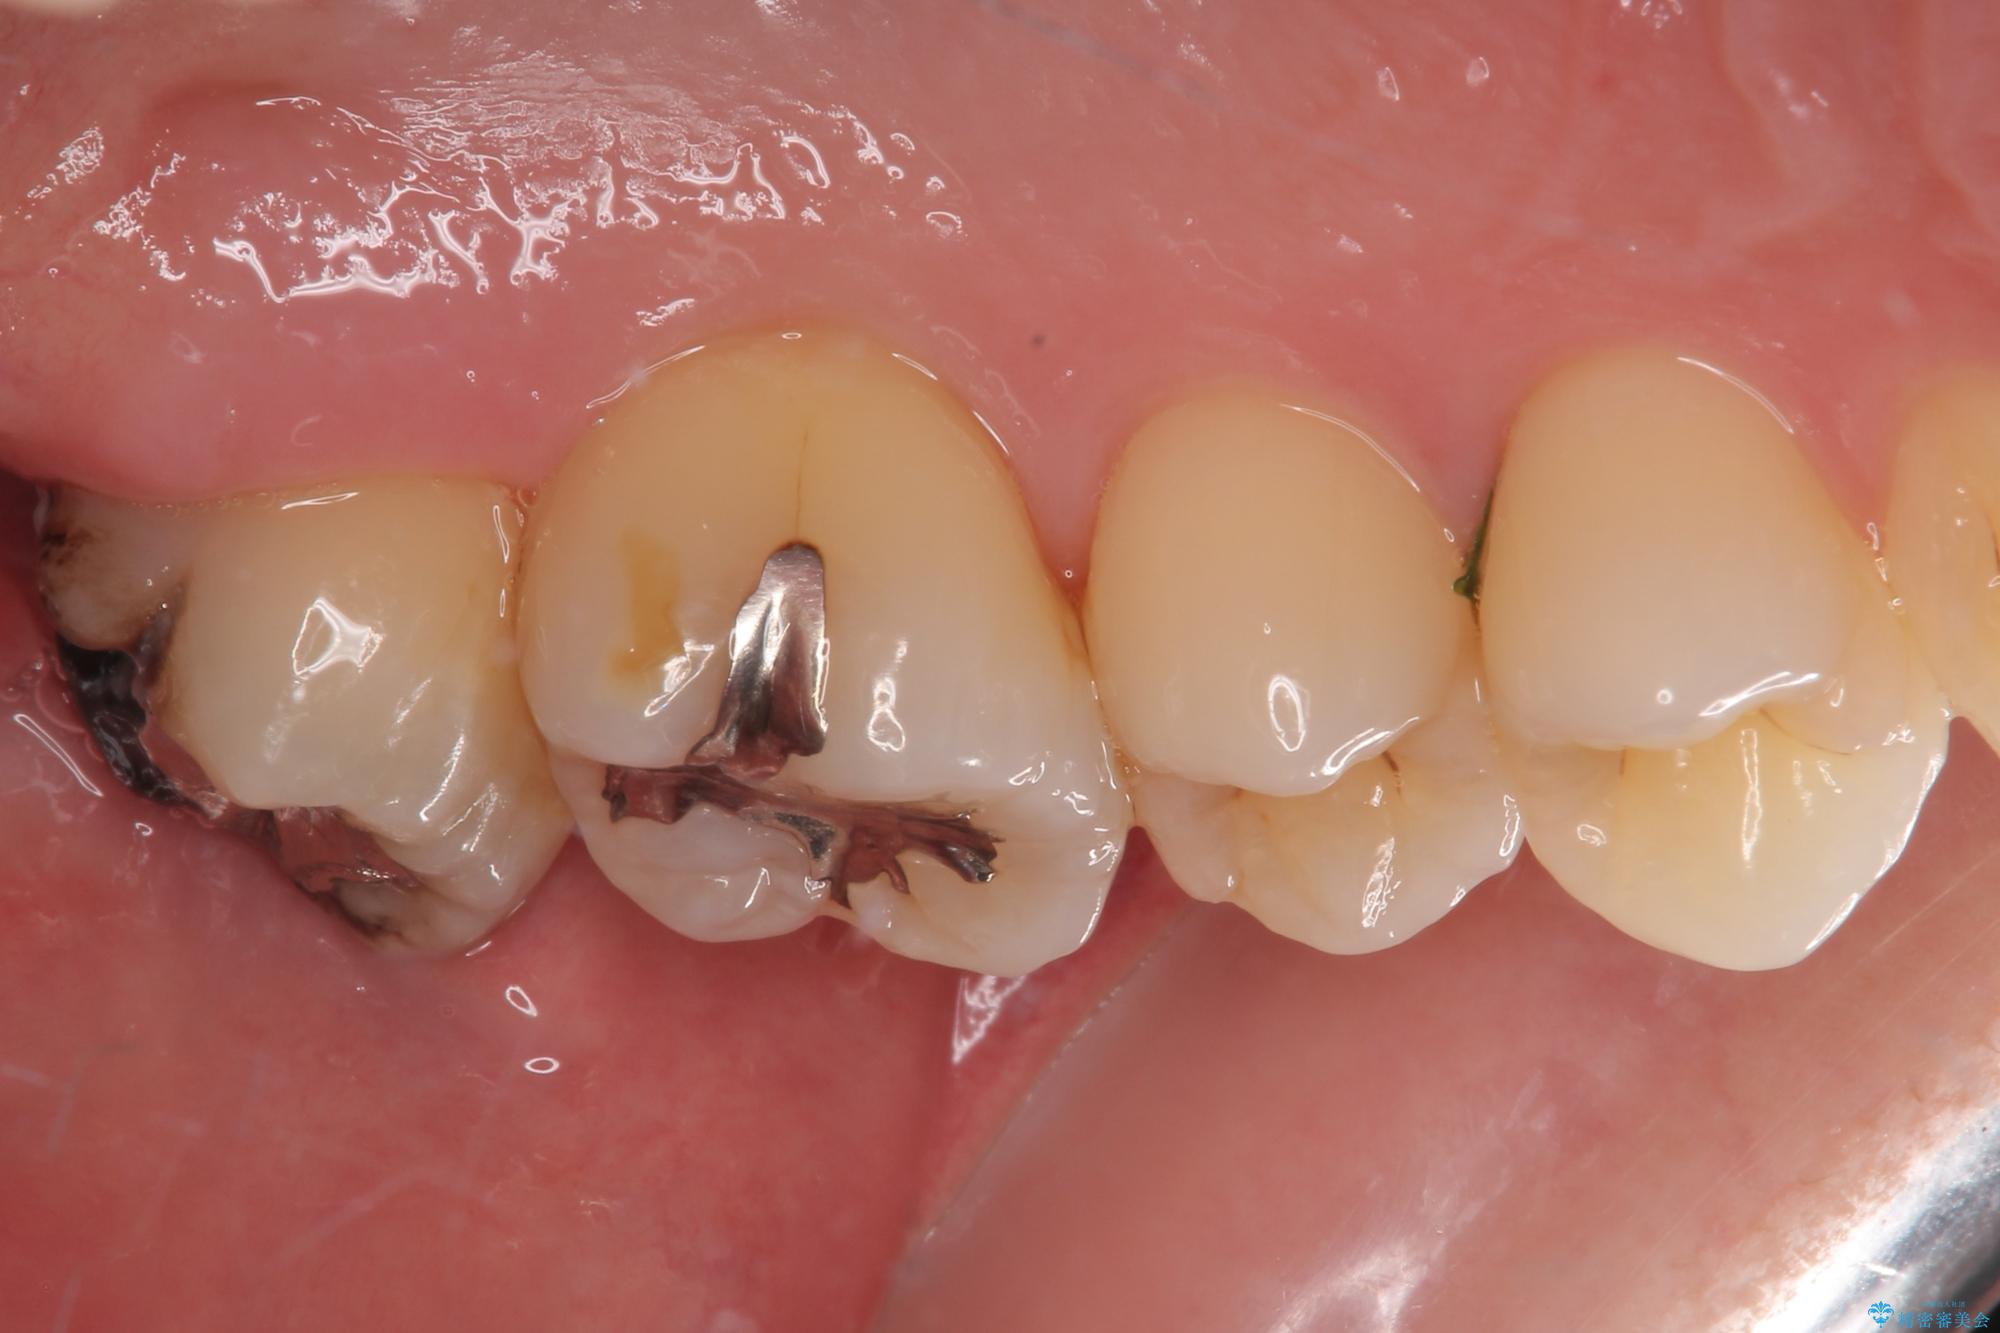

矯正治療により処置が可能な位置に歯が移動したため、オールセラミッククラウンにて補綴治療を行うこととしました。

歯列が移動したとはいえ、左右ともに後方傾斜しており、むし歯の除去、形成(形を整える)、型取りの全てが非常に困難な処置となりました。

セラミッククラウンの適合はレントゲン写真からも分かる通り、境界がぴったりと合った、高適合のものとなりました。